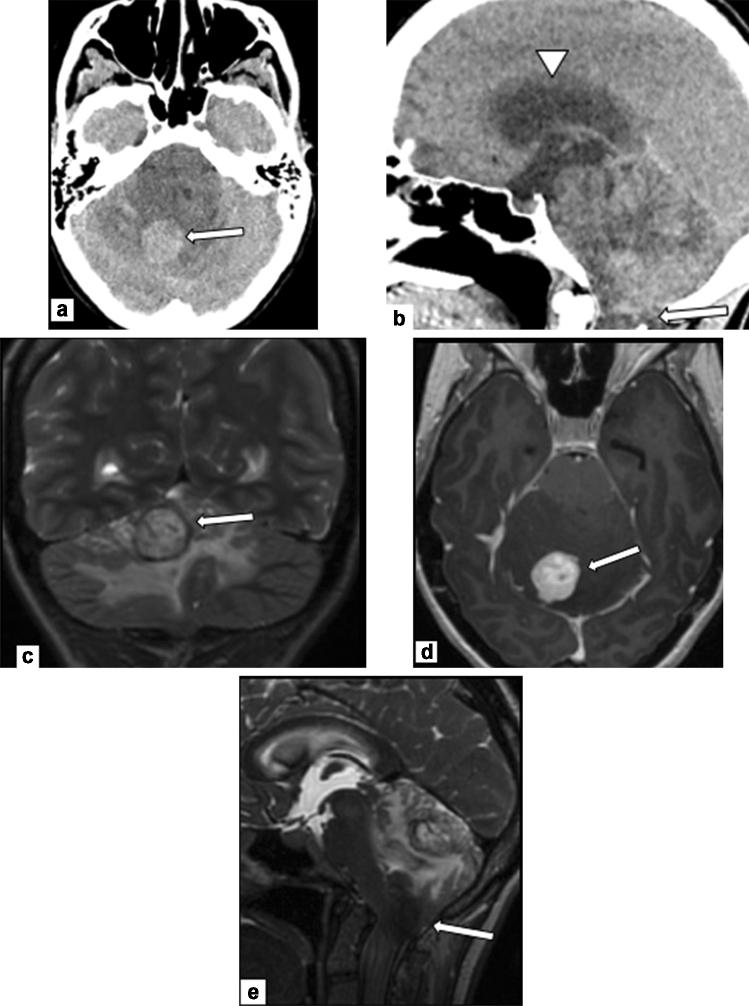

Pregnancy-associated cancer (PAC) occurs in approximately 1 in 1000 pregnancies, and the incidence is expected to rise due to delayed childbearing (Silverstein et al. in JCO Oncol Pract 16:545-557, 2020; Woitek et al. in ESMO Open 1:e000017, 2016). Diagnosis and management of PACs are challenging and diagnosis is often delayed as symptoms may overlap with physiologic changes of pregnancy (Jha et al. in RadioGraphics 42:220005, 2022). These patients are best cared for by a multidisciplinary healthcare team composed of experts (Silverstein et al. in JCO Oncol Pract 16:545-557, 2020). Management of these patients must balance optimal maternal care with potentially harmful fetal effects. This involves honest, forthright, and sometimes difficult discussions between the care team and the patient throughout the entirety of care. Radiologists play a significant role in timely cancer diagnosis, staging and follow-up during and after pregnancy, accurate determination of gestational age, and in assessing fetal growth and well-being throughout pregnancy.

妊娠相关癌症(PAC)在大约每 1000 次妊娠中发生 1 次,由于生育年龄推迟,其发病率预计将会上升(Silverstein 等人,在 JCO Oncol Pract 16:545-557,2020;Woitek 等人,在 ESMO Open 1:e000017,2016)。PAC 的诊断和管理具有挑战性,且诊断往往被延误,因为症状可能与妊娠的生理变化相重叠(Jha 等人,在 RadioGraphics 42:220005,2022)。这些患者最好由多学科医疗团队的专家进行治疗(Silverstein 等人,在 JCO Oncol Pract 16:545-557,2020)。这些患者的管理必须在最佳的母婴护理与胎儿潜在有害影响之间取得平衡。这需要护理团队与患者在整个护理过程中进行坦诚、直率,有时甚至是困难的讨论。放射科医生在妊娠期间和妊娠后及时进行癌症诊断、分期和随访、准确确定胎龄以及评估胎儿生长和健康方面发挥着重要作用。